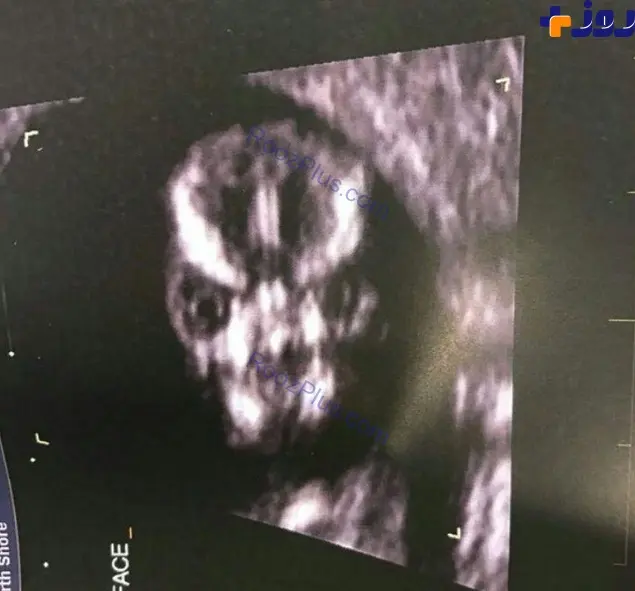

عکس سونوگرافی بارداری وحشتناک زنی که با یک سگ ازدواج کرده/ تصویر

به گزارش منیبان به نقل از رصد ورزشی، زن که مدتی متوجه تغییرات هورمونی در بدن خود شده بود با مراجعه به بیمارستان و آزمایشات اولیه پی برد که باردار شده است.

بارداری این زن از سگ خانگی اش که از نژاد دوبرمن بود پزشکان بیمارستان را به وحشت و تعجب انداخت.

با آزمایشات اولیه پزشکان پی بردند که این بارداری برای زن جوان به شدت خطرناک است .

پزشکان اعلام کردند که او باید حتما سقط جنین سگ انجام دهد .